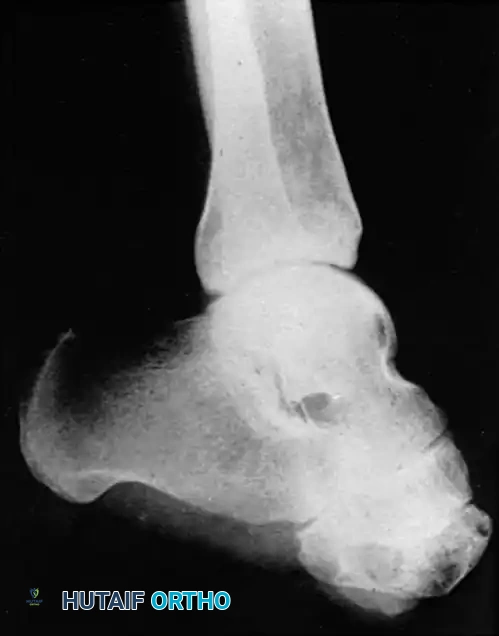

Midfoot amputations (Lisfranc and Chopart levels) historically carried high failure rates due to severe biomechanical imbalances. Severing the insertions of the dorsiflexors (tibialis anterior, extensor hallucis longus, extensor digitorum longus) leaves the powerful plantarflexors (triceps surae) unopposed. This inevitably leads to a severe equinus deformity, resulting in distal stump breakdown and ulceration.

Severe equinus deformity

To prevent this, simultaneous percutaneous Tendo-Achilles Lengthening (TAL) or formal heel cord tenotomy is mandatory during midfoot amputations. Roach and McFarlane demonstrated that prophylactic heel cord tenotomies prevent fixed equinus deformities, allowing successful ambulation with simple prosthetic devices and drastically reducing the need for revision to a higher level.